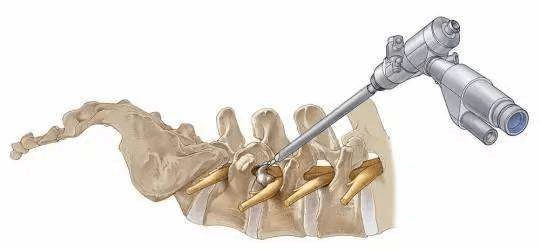

经皮内镜下椎间盘摘除术

技术简介:在局部麻醉(部分采用硬膜外麻醉或全身麻醉)下,应用脊柱内镜系统,通过不到1厘米的切口完成椎间盘摘除,解除神经受压。

技术特色:由于脊柱内镜系统大多采用水介质,术中不停冲洗手术部位,可大大减少术后感染的风险;高清显微内镜将术野放大20倍左右,即使微小的毛细血管和神经也能够清晰辨认,手术操作更加精细,止血更加彻底,出血量约20毫升左右,较传统开放术式创伤大大减小,恢复更快(术后3天左右即可下地活动,正常生活),并发症更少;手术全程在患者清醒的意识状态下完成,更加安全,手术对患者身体条件要求较传统开放术式更低,部分无法耐受开放手术的患者亦可通过脊柱内镜治疗。

适应症:颈、胸、腰椎间盘突出、脱出、游离,上述疾病经正规保守治疗3月无效,严重影响生活质量,症状进行性加重,出现较严重的神经、脊髓损害者,需手术治疗。